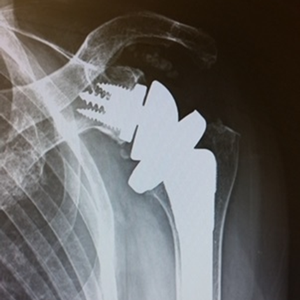

整形外科における手術の役割 肩腱板断裂治療のアルゴリズム 不全断裂 小断裂 中~大断裂 一次修復不能広汎性断裂 保存療法(リハビリ:運動療法/物理療法) 手術療法 関節鏡下腱板修復術 腱移行術、腱移植術、リバース型人工関節 腱板断裂の治療の基本は保存療法ですが、それが反応しない場合には、関節鏡下腱板修復術が適応されます。 修復前 修復後 関節鏡下腱板修復術は「肩に小さな穴を数か所開け、関節鏡で中をのぞきながら縫い合わせる方法」で、私の得意分野です。 不全断裂 小断裂 中~大断裂 一次修復不能広汎性断裂 保存療法(リハビリ:運動療法/物理療法) 手術療法 関節鏡下腱板修復術 腱移行術、腱移植術、リバース型人工関節 縫いきれないほどの大きな断裂には、腱の移植や人工関節が必要になります。 手術を望まない方へは、間葉系幹細胞を用いた再生医療の提供に取り組んでいます。